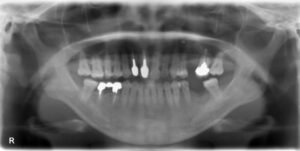

下顎臼歯2本欠損症例

BEFORE AFTER 50歳男性/下顎2本欠損/インプラント埋込手術 【治療内容】 右下第二小臼歯、第一大臼歯が欠損…